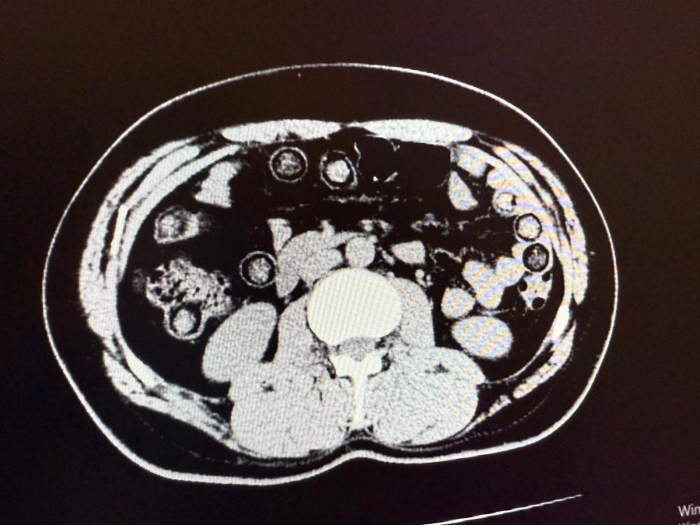

Muş Devlet Hastanesi'ne götürülen şüphelilerin yapılan kontrollerinde midelerinde uyuşturucu olduğu belirlendi.

Şüphelilerin midesinden 94 kapsül içerisinde 928 gram sentetik uyuşturucu ele geçirildi.